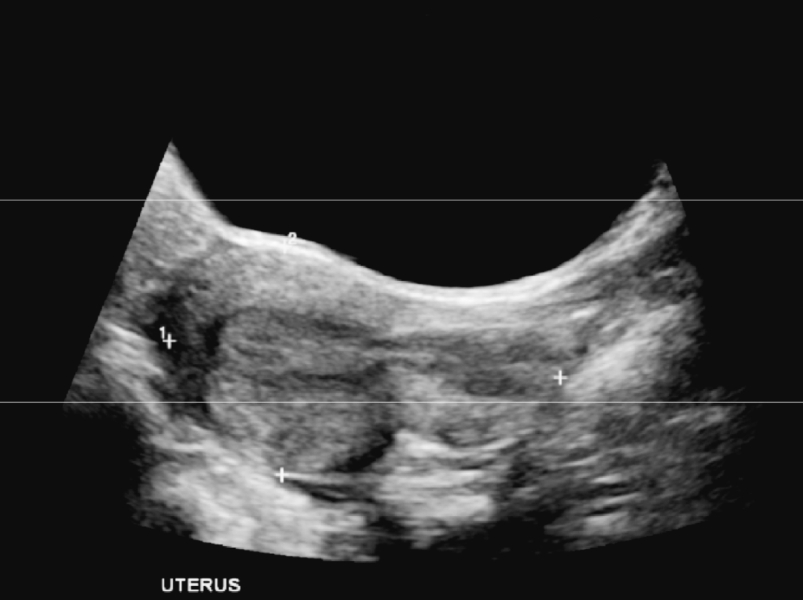

Hi All, I haven't been back on for a bit I been feeling crazy and anxious and a bit crappy. I went for another ultrasound and basically the same thing has happened as I get bigger and cravings approx 17 weeks and still silence to concentrate on the scan I feel silenced. I'm in the midst of seeking a 2nd opinion and trying to settle myself and find motivation and energy but my instincts and intuition are driving me to find answers. Otherwise from strong pregnancy symptoms religiously by the book to the fine tune. My uterus is still retroverted and flexed, I'm having terrible back ache and swimming to see if it might position forward and gentle yoga. Once again it's been said in literature that retroverted uterus babies may not be seen until 20 weeks, movements on 22 to 24 weeks and showing a very late bump so I'm,waiting. Still abstinent and presented to the ER thus week from dizzy spells and fainting feelings. BP good, GTG of heart good nothing else again sent home without back relief or advice to manage. I nearly fainted walking to collect mail the other day saw stars and staggered back inside. Anyone have any further ideas besides getting another opinion please I thought I seen a face on pic on the last scan different and bigger than my October one on edge. Even once I thought it was a head lying transverse across abdomens and leg bent over the body.

@MissBee02 have they offered you a transvaginal ultrasound as I know that can help identify with a retroverted uterus . ( I remember from a thread a long time ago a woman had mentioned that she was offered one due to her retroverted uterus ) .